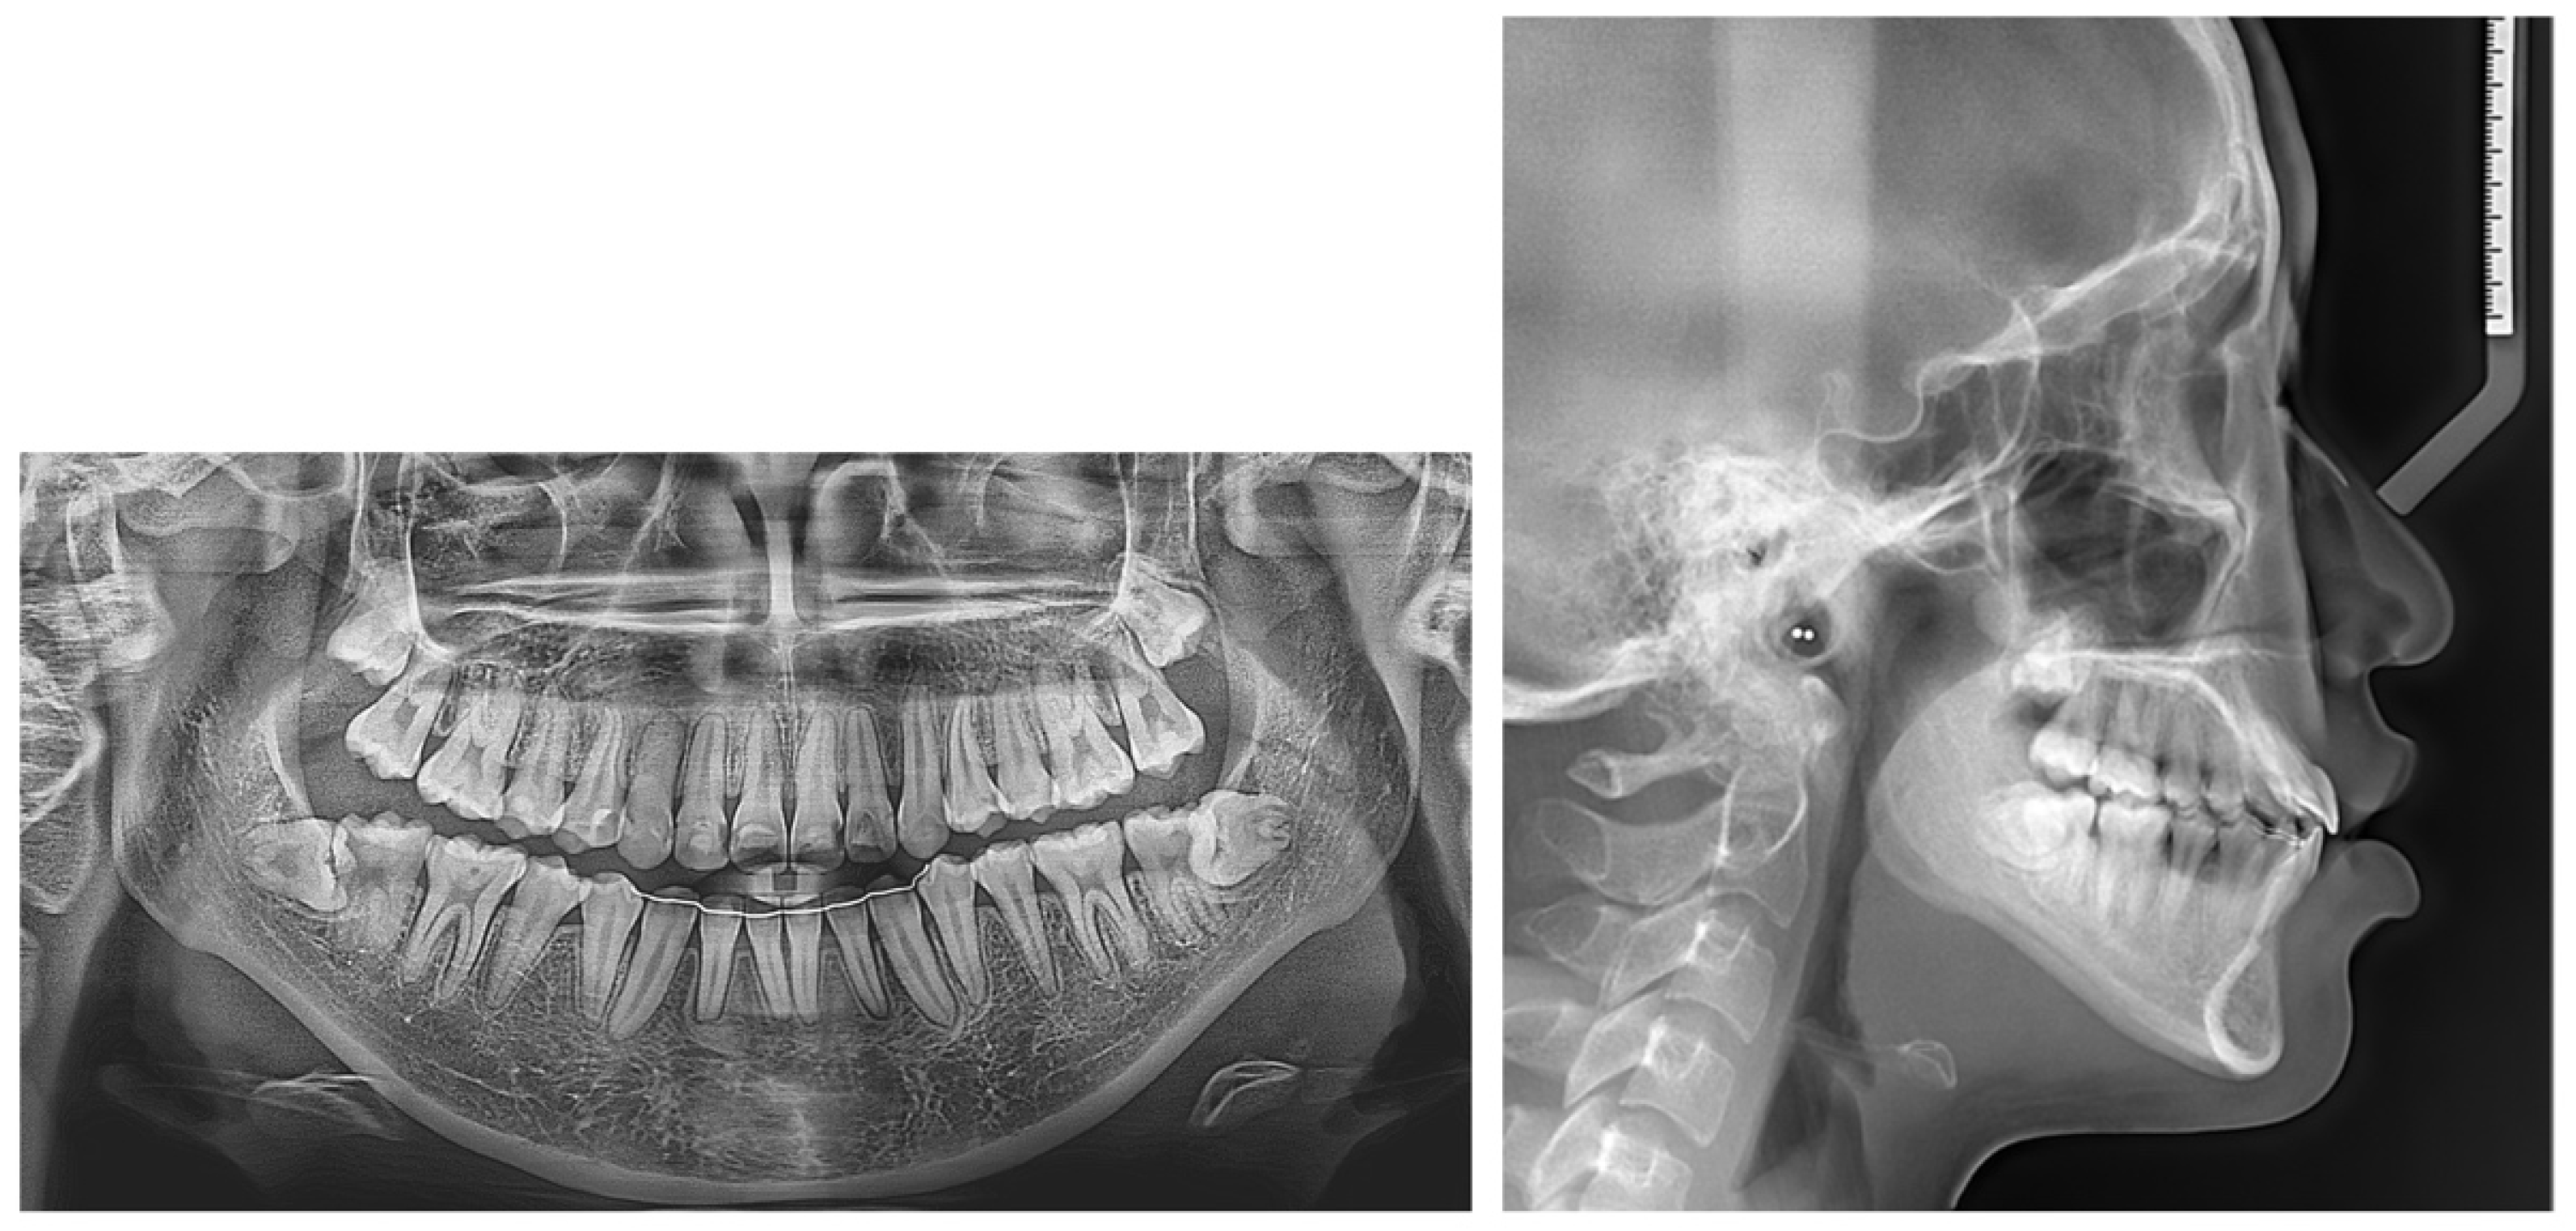

2. Case Presentation

2.1. Diagnosis and Etiology